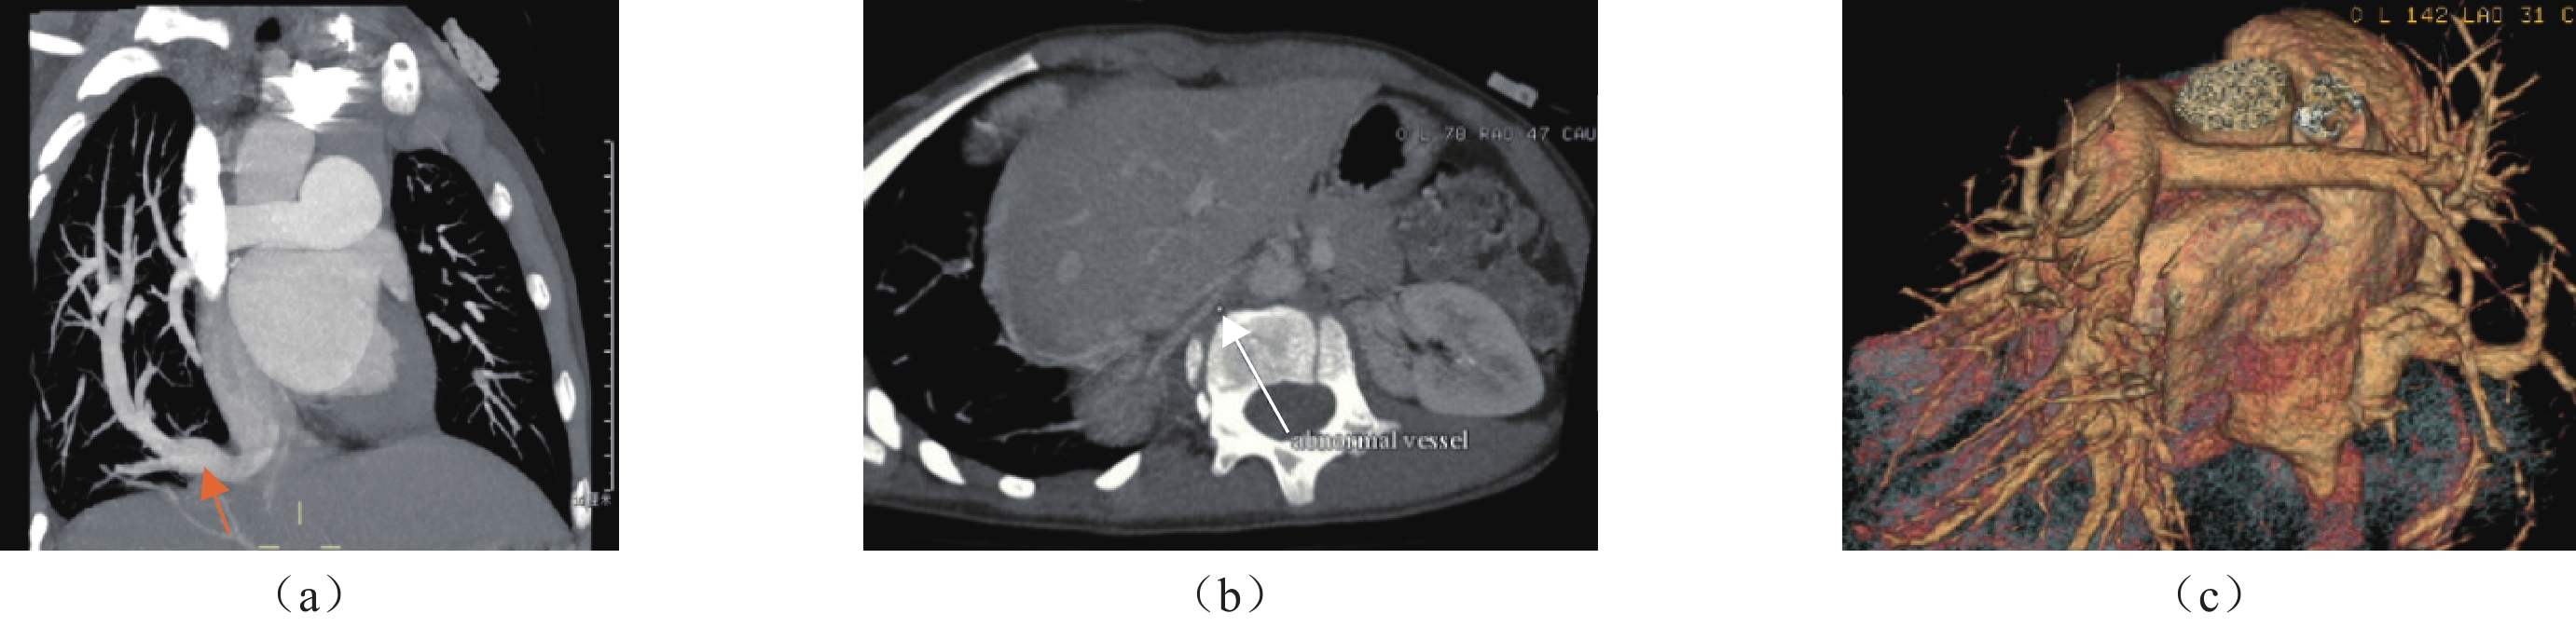

婴儿型弯刀综合征15例患儿中10例为完全右肺静脉异位引流至下腔静脉,其中3例异位引流入下腔静脉处狭窄梗阻(图1),该3例患儿行部分肺静脉异位连接弯刀综合征矫治术,术后患儿随诊复查无不适,1例合并房间隔缺损及肺动脉高压,1例合并房间隔缺损、动脉导管未闭及肺动脉高压,该2例患儿均行房间隔修补术的同时行部分肺静脉异位连接弯刀综合征矫治术,合并动脉导管未闭的患儿还行动脉导管结扎术,其余5例患儿未行手术。

成人型弯刀综合征13例中7例为完全右肺静脉异位引流至下腔静脉(图2),其中1例因胸廓畸形(鸡胸)行部分肺静脉异位连接弯刀综合征矫治术;6例为右下肺静脉异位引流至下腔静脉,其中2例明确诊断后,药物对症治疗期间反复肺炎行部分肺静脉异位连接弯刀综合征矫治术,2例合并叶外型隔离肺行介入栓堵治疗体动脉供血。

另外,由于弯刀综合征存在程度不等的心脏及血管畸形,对于分流量大于50%、异位引流肺静脉狭窄、肺动脉高压和隔离肺时需手术治疗[8]。有文献报道可根据CT增强后的MPR测量弯刀静脉汇入下腔静脉角度的大小采用不同的手术方法[9]。本组28例患儿均行胸部CT增强分期扫描,分别于动脉期及静脉期进行扫描,利用增强后的图像数据进行MPR及MIP重建对心脏、血管进行评估,其中临床症状较重的婴儿型患儿有3例在MPR及MIP图像上可见异位引流处狭窄梗阻(图1),2例可见合并了心内畸形—房间隔缺损及肺动脉主干明显增粗,其中1例还合并了较粗大的动脉导管未闭,并经手术证实,术后患儿情况良好。2例成人型患儿经MPR及MIP重建清晰显示了于膈肌水平主动脉分别发出1分支及2支血管供应肺外型隔离肺(图2),之后行介入手术,栓堵的该异常体动脉,术后患儿恢复良好。